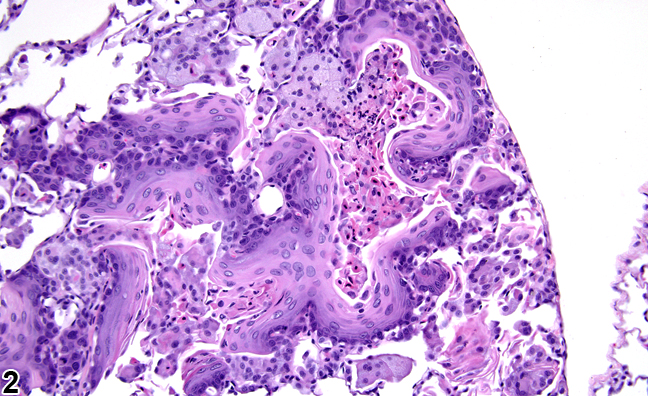

- Ung thư biểu mô: Những khối u này hình thành từ các tế bào biểu mô, có trong da và mô bao phủ hoặc đường viền các cơ quan của cơ thể. Ung thư có thể xuất hiện ở dạ dày, tuyến tiền liệt, tuyến tụy, phổi, gan, ruột kết hoặc vú. Đây là một loại khối u ác tính phổ biến.